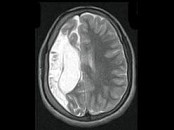

男,35岁,有颅脑外伤史,MRI图像,最可能的诊断是()

• A.脑软化

• B.脑萎缩

• C.脑积水

• D.脑穿通畸形囊肿

• E.脑实质占位